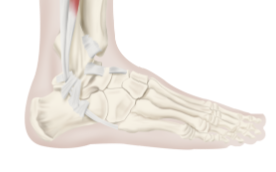

인대란 뼈와 뼈, 뼈와 근육을 연결해주는 조직으로, 인대를 통해 관절은 안정성을 유지하고 움직임을 제어합니다. 인대는 뼈에 밀착되어 있으며 유연하면서도 강한 섬유로 이루어져 있습니다. 인대는 다양한 원인으로 인해 손상될 수 있으며, 인대 손상은 관절의 움직임 제한, 통증, 부종 등의 증상을 유발할 수 있습니다. 인대 손상은 주로 운동이나 스포츠, 교통사고 등으로 발생하며, 적절한 치료를 받지 않으면 장기적인 합병증을 유발할 수 있습니다. 따라서 인대 손상 시 적절한 치료와 예방이 필요합니다.

발목 인대파열은 발목을 지지하고 안정성을 유지하는 역할을 하는 인대가 부상을 입은 상황입니다. 발목 인대파열의 증상은 다음과 같습니다.